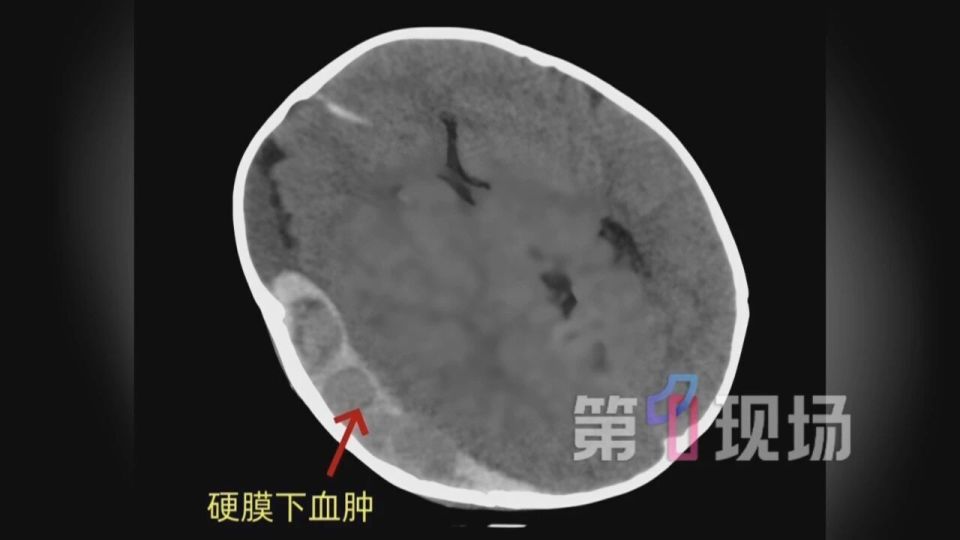

CT检查发现,小元颅内右侧有一块巨大的硬膜下血肿,出血量达到100毫升,脑组织被巨大血肿“压”得变形、移位非常严重,已形成严重脑疝